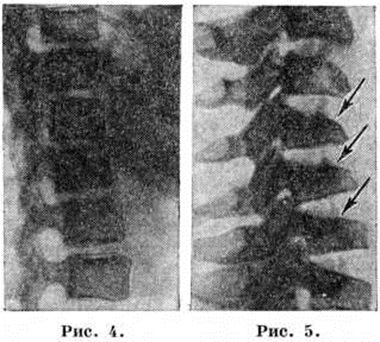

Сглаженность (уплощение) физиологический поясничного Лордоз наблюдается у лиц с небольшим патологический кифозом, формирующимся на уровне Лордоз.

При этом, как правило, наблюдается уплощение и физиологический грудного кифоза, вследствие чего позвоночник становится выпрямленным (рисунок 4). Чаще всего подобная деформация возникает при юношеском кифозе за счёт снижения высоты поясничных дисков и снижения высоты тел поясничных позвонков в передних отделах. Аналогичный механизм уплощения поясничного и шейного Лордоз наблюдается при компрессионном переломе тел позвонков или их синостозе, при деструктивных процессах в поясничном отделе позвоночника (например, опухоли, туберкулёзный спондилит).

В шейном отделе гиперлордоз возникает у лиц с гиперкинетической формой пареза, но чаще в этом отделе наступает его сглаженность, которая выявляется после травмы (подвывих, вывих, компрессионный перелом тела позвонка), в связи с чем эта сглаженность шейного Лордоз приобретает важное диагностическое значение (рисунок 5). При врождённом или приобретённом синостозе тел II — III шейных позвонков на месте Лордоз может формироваться кифоз, так же как и при разрушении или компрессии тел шейных позвонков.